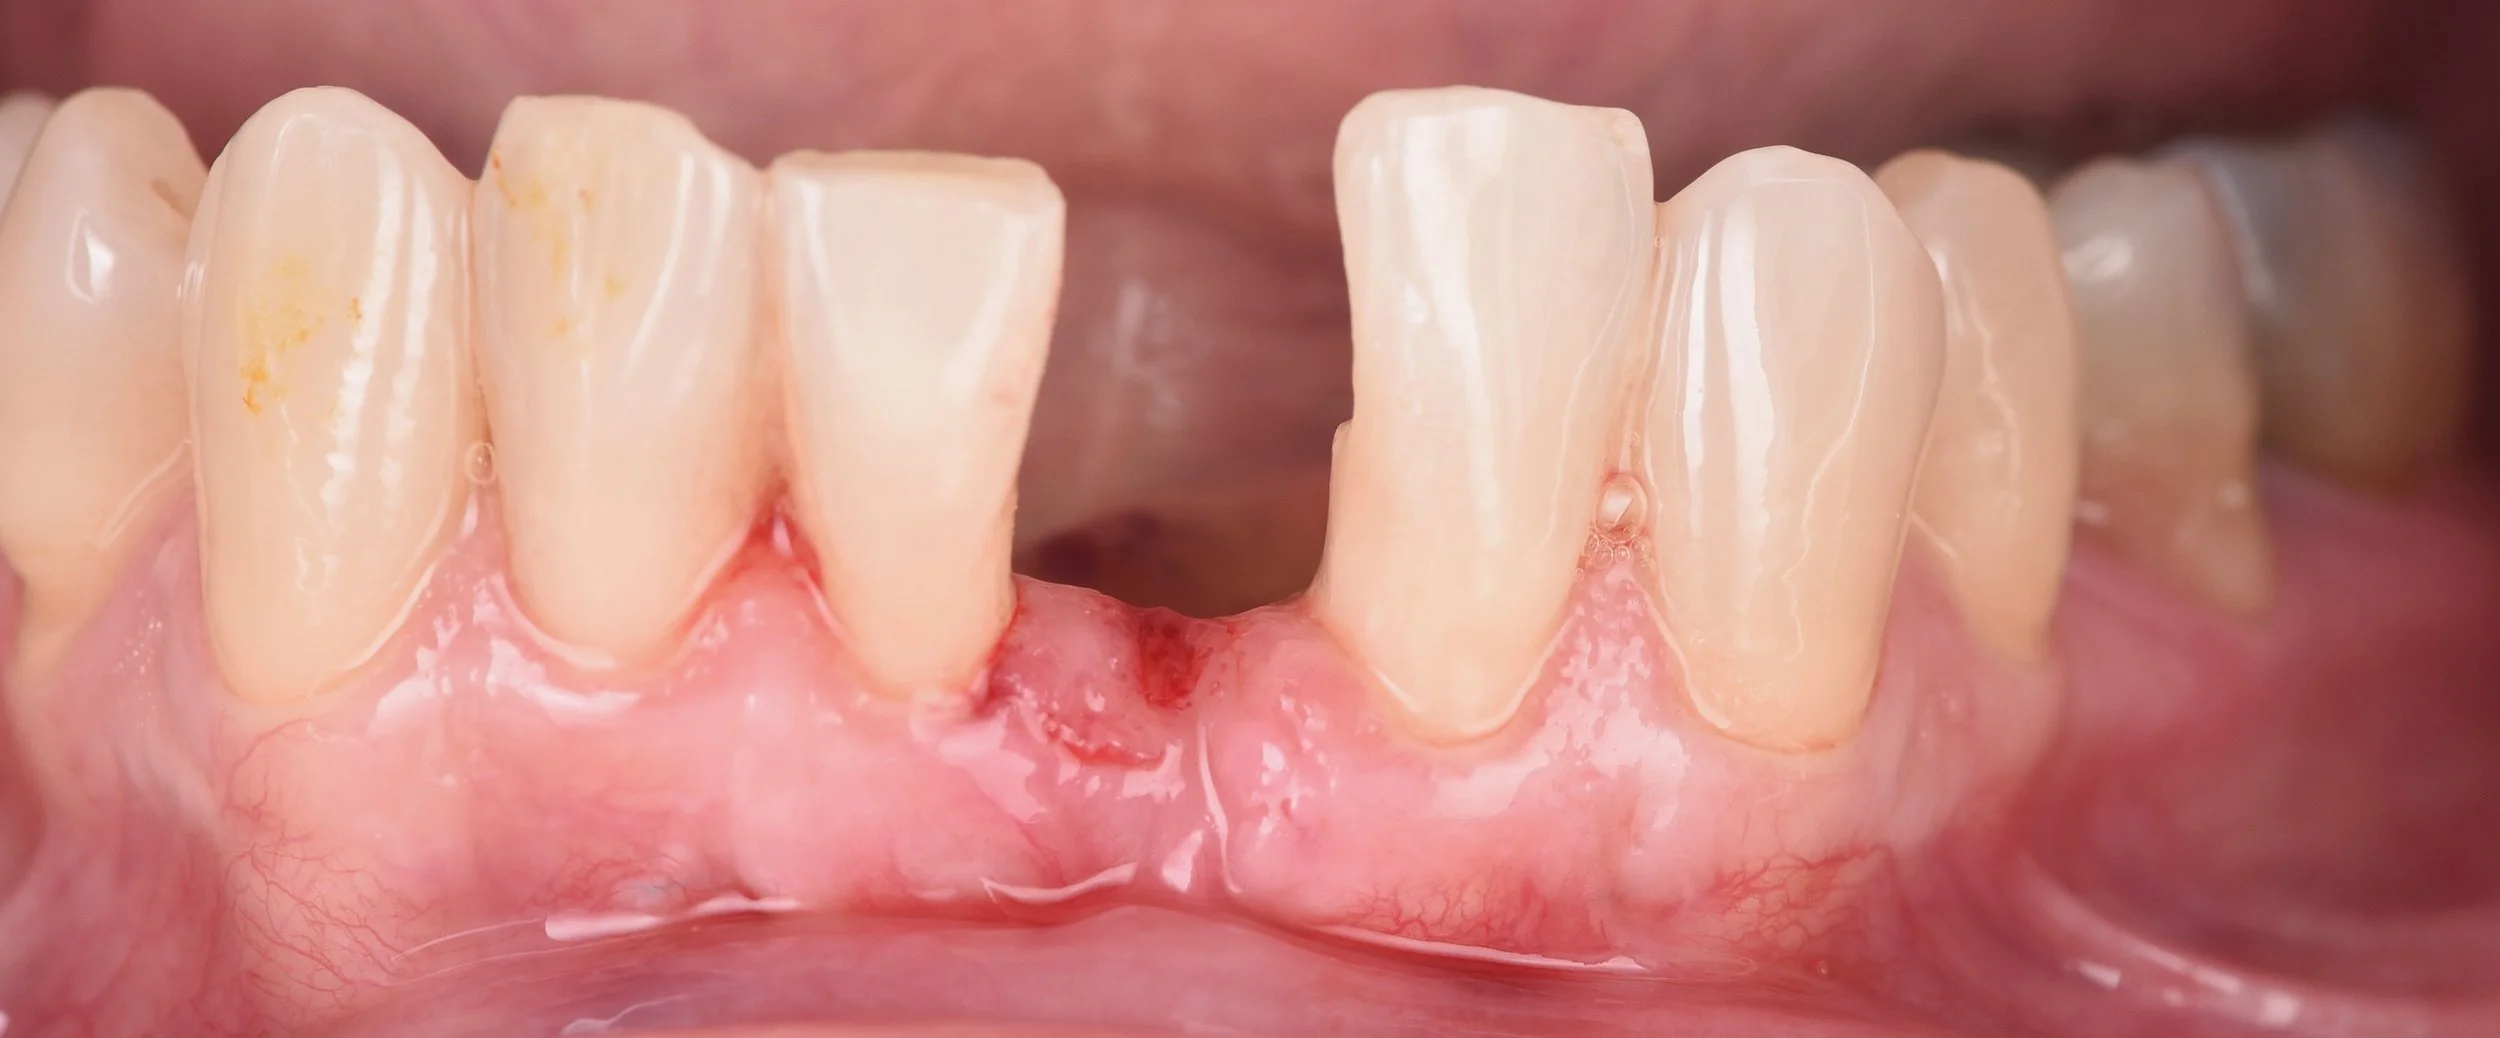

• Cas particulier de la mandibule

• Recouvrement de l’incisive centrale mandibulaire

• Comment optimiser et rendre reproductible les greffes mandibulaires

• La tunnelisation est-elle toujours LA solution ?